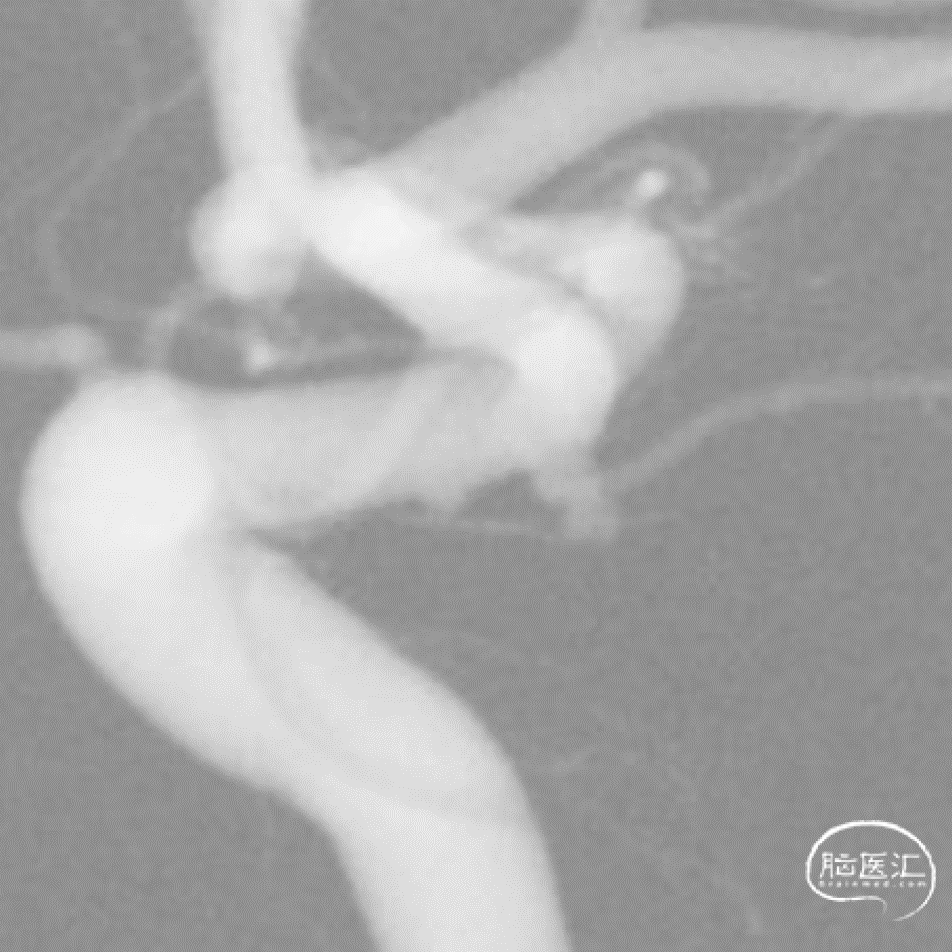

Roadmap

微导管超选

Galaxy G3 MINI 1mm*1cm的mini(强生)

术后情况/术后即刻:动脉瘤不显影

支架远端定位和释放

释放过程